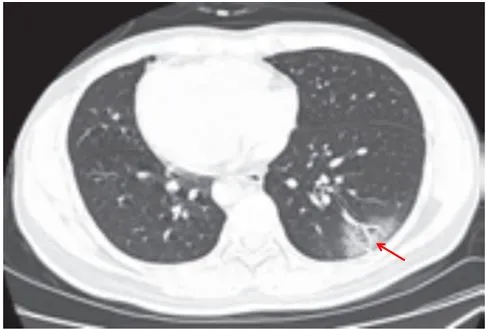

病灶以肺外围背侧为主,以两肺下叶为著,与胸膜常紧贴,提示新冠肺炎病变多首先侵犯皮层肺组织的细支气管及肺泡上皮,病灶分布逐步从外周向中央扩展(图 2-1)

图2-1 早期病灶多数分布贴近胸膜(共4张)